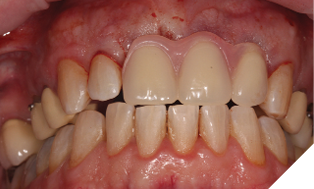

The existing metal ceramic bridgework was thick and bulky, but the patient was used to it. The patient also didn’t have any pain or discomfort yet from the slightly loose bridge or dental caries. The patient was most concerned the bridge would suddenly come out and would have a space (Figs. 3-4).